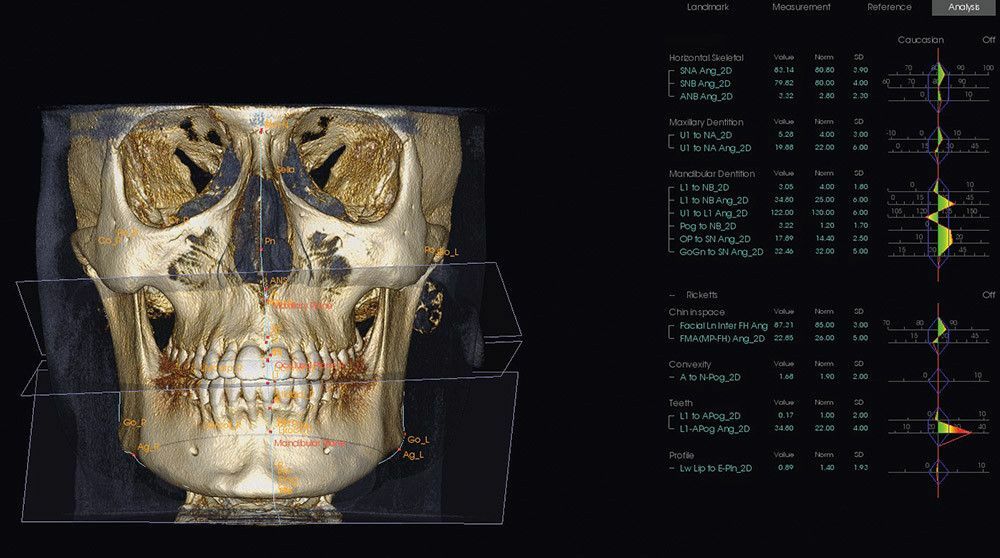

Ортодонтия: план лечения с повышенной точностью